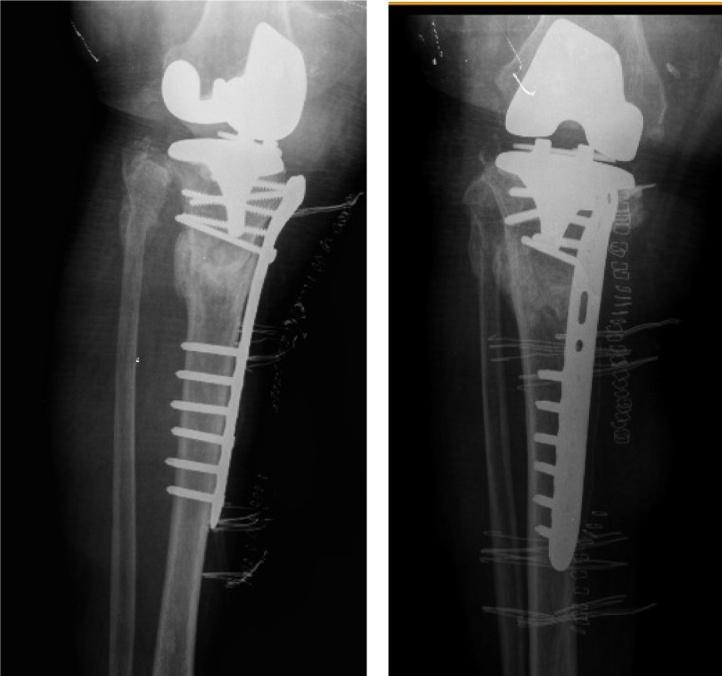

PRESENTATION OF CASE

75-year-old male patient with bilateral knee osteoarthritis had not benefited from conservative treatment methods previously applied. Left TKA was applied. In the second month postoperatively, periprosthetic tibial fracture was identified and osteosynthesis was implemented with locked tibia proximal plate-screw. Bone union in 12 weeks was observed in his follow-ups. After 15 months of his first operation, TKA was applied to the right knee. Postoperatively in the second month, as in the first operation, periprosthetic tibial fracture was detected. Osteosynthesis with locking plate-screw was applied and union in 12 weeks was observed in his follow-up. He was seen mobilized independently and without support in the last control of the case made in the 24th month after the second operation.

一名75岁男性患者患有双侧膝关节骨关节炎,之前采用的保守治疗方法均未见效。实施了左侧全膝关节置换术。术后第二个月,发现假体周围胫骨骨折,并采用锁定胫骨近端钢板螺钉进行了骨固定。随访观察到12周时骨愈合。首次手术15个月后,对右侧膝关节实施了全膝关节置换术。术后第二个月,如同首次手术一样,检测到假体周围胫骨骨折。采用锁定钢板螺钉进行骨固定,随访观察到12周时愈合。在第二次手术24个月后的最后一次病例检查中,发现他能够独立活动且无需支撑。